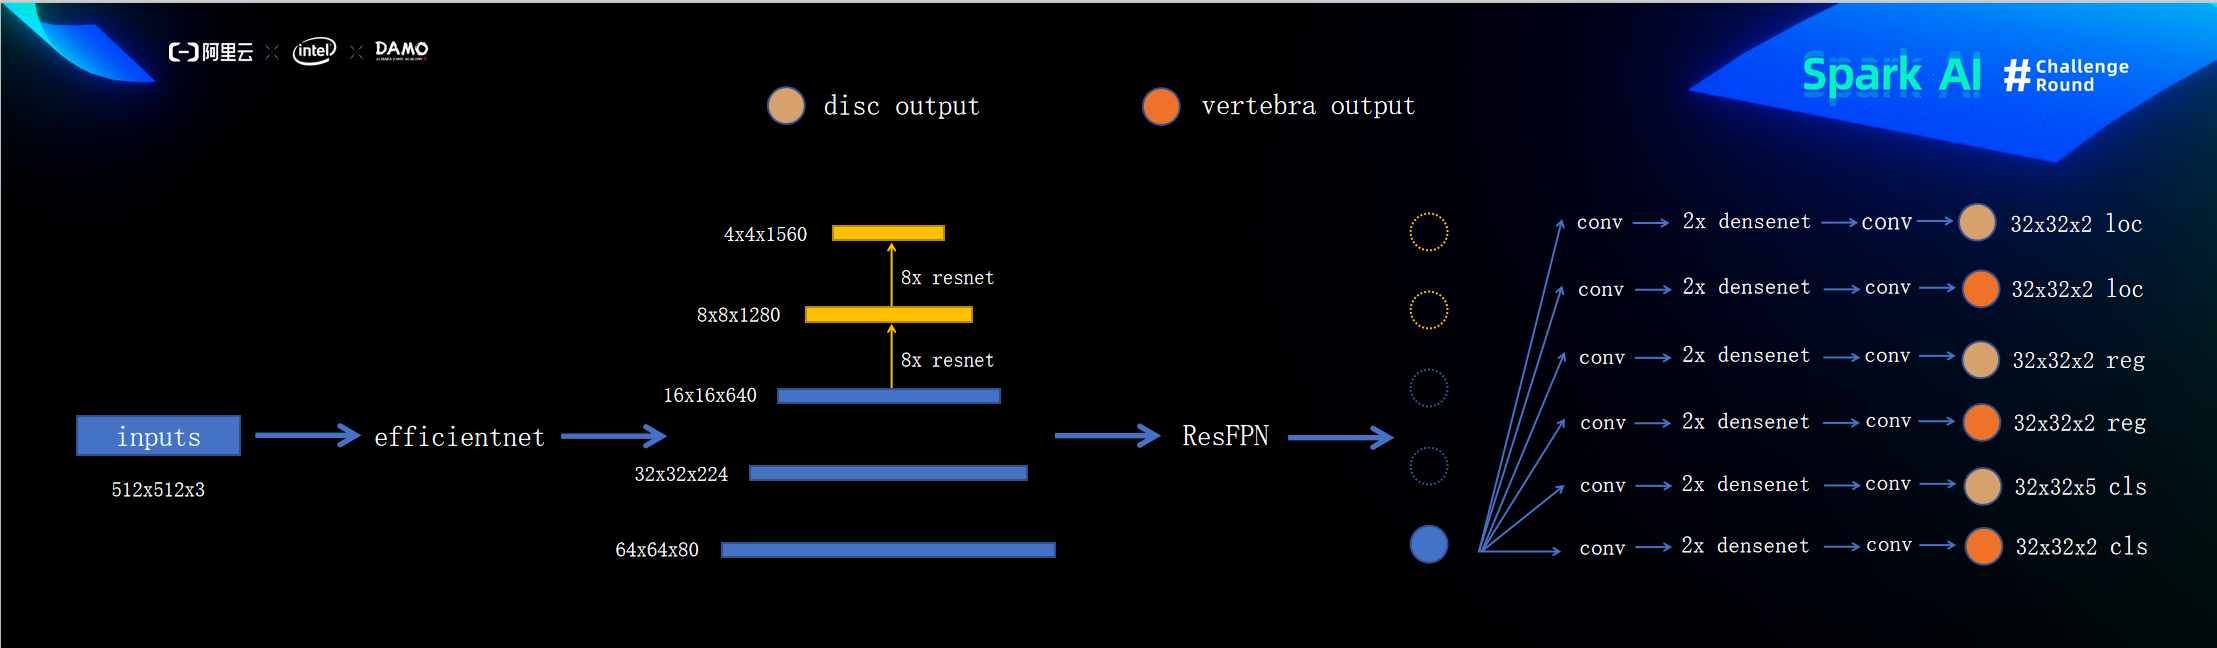

本次比赛我使用的是类似于EfficientDet 的物体检测方法(虽说类似,但其实差别也很大),首先数据经过统一resize到(512,512,3)之后经过backbone(efficientnet b7)输出三层的feats[(64,64,80)(32,32,224)(16,16,640)],由于512x512的图片经过efficientnet输出的特征图最小只有16x16,所以各使用8层的resnet继续采样得到8x8和4x4大下的特征图,之后经过ResFPN(一个参照resnet设计的残差FPN)进行特征融合,然后取最大的特征图即64x64来用于最后输出头的输入,输出头的第一个操作就是继续采样得到32x32大小的特征图 ,即最后的物体检测操作其实是在32x32大小的特张图上进行,loc用于判断背景或者物体(iou<0.3为背景,0.3<iou<maxiou不输出loss,iou==maxiou即为物体),reg用于坐标的回归(iou<0.6不输出loss,iou>0.6正常输出loss),cls用于判断物体的症状(iou<0.6不输出loss,iou>0.6正常输出loss)。

模型结构图